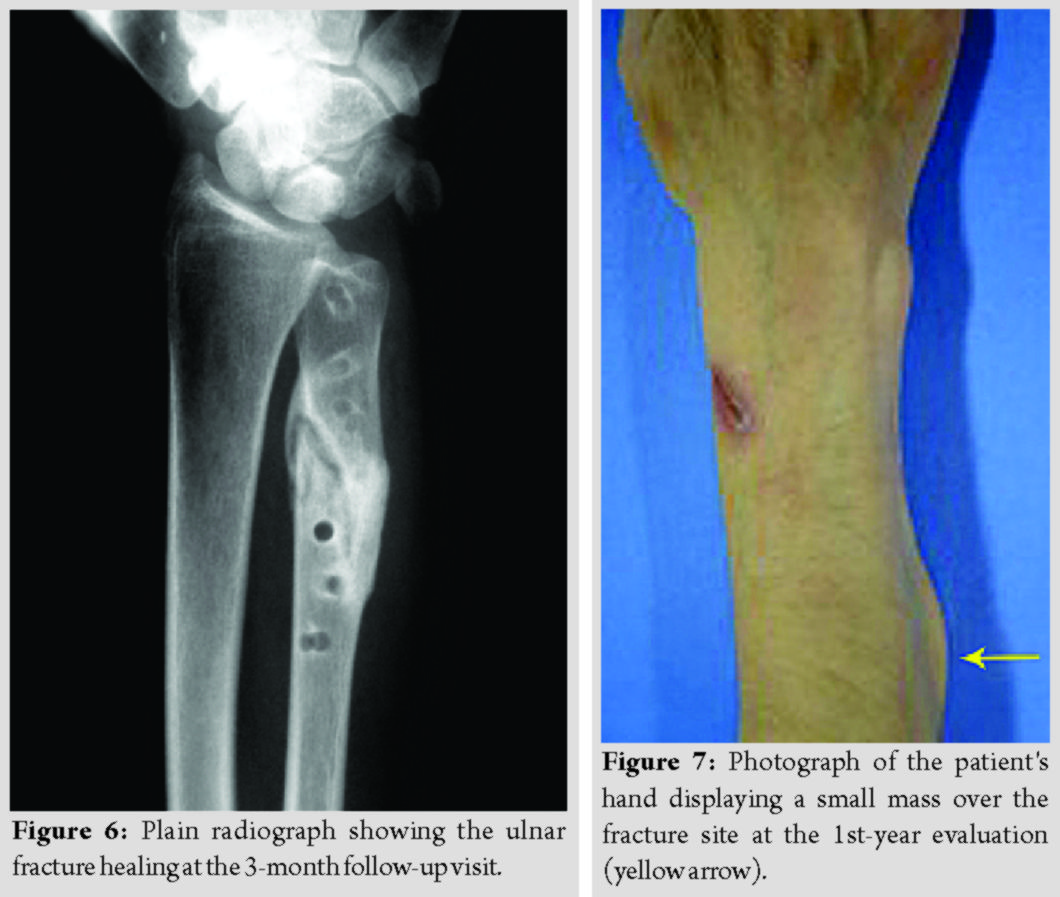

The fragmented absorbable plate was removed (Fig. 5), and a 3.5 mm metallic plate and screws were used for refixation. Subsequently, all fractures healed uneventfully (Fig. 6). The patients’ grip strength and DASH score at 9 months are presented in Table 2.

During the 10 years of clinical follow-up assessments, no severe soft-tissue reaction to the absorbable polymer materials was observed. In one patient, a small, palpable, painless mass over the fracture site was apparent at the 1st-year evaluation and remained at the same size since then (Fig. 7). Debridement was not decided because we did not notice any further signs of inflammation.